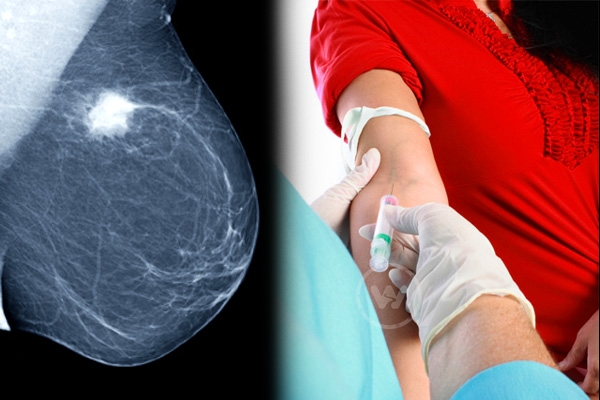

(Image source from: Blood Test to Predict the Risk of Breast Cancer!})

Women of both developed and less developed states are victims of the breast cancer, which is remaining horrific for the families of the victims. According to a study that was published in Metabolomics, a new type of blood test could predict the possibility of getting the risk in coming 2-5 years.

The new method would benefit most of the women in long-term with precautions. So far mammography was one of the diagnosing methods to detect the presence of cancer in breasts. The mammography could able to diagnose the newly developed breast cancer with a sensitivity of 75 per cent, while new blood test is claimed to be maintaining the sensitivity of 80 percent.

If the pre-detecting or predicting technology gives good results, it will help crores of women across the globe to take precautions to prevent the life threatening disease. The mammography and other diagnosing methods were able get detect the disease after hitting by the breast cancer, that in later stages in most of the cases.